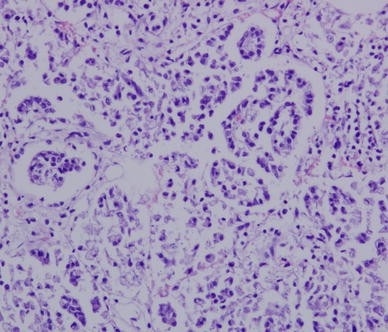

After H&E staining of the lungs, which were obtained from infected sheep, proliferation of alveolar epithelial cells was confirmed, which were found to burst into the alveolar cavity like the papillary. In addition, lymphocytic infiltration into the pulmonary interstitia was observed (Fig. 2). Abundant proliferative collagen fibers were also observed in the alveolar mediastinum (Fig. 3a). OPA virus-like particles were found in the lung, and the length of the virus diameter was determined to be approximately 100–125 nm, with small bump-like structures existing on the surface of the virus particles by TEM analysis (Fig. 3b).

Fig. 2

Histological observations after H&E staining of lung from infected sheep. Alveolar epithelial cell proliferation and lymphocyte infiltration in pulmonary interstitial cells were observed (H&E staining procedure, ×200 magnification)